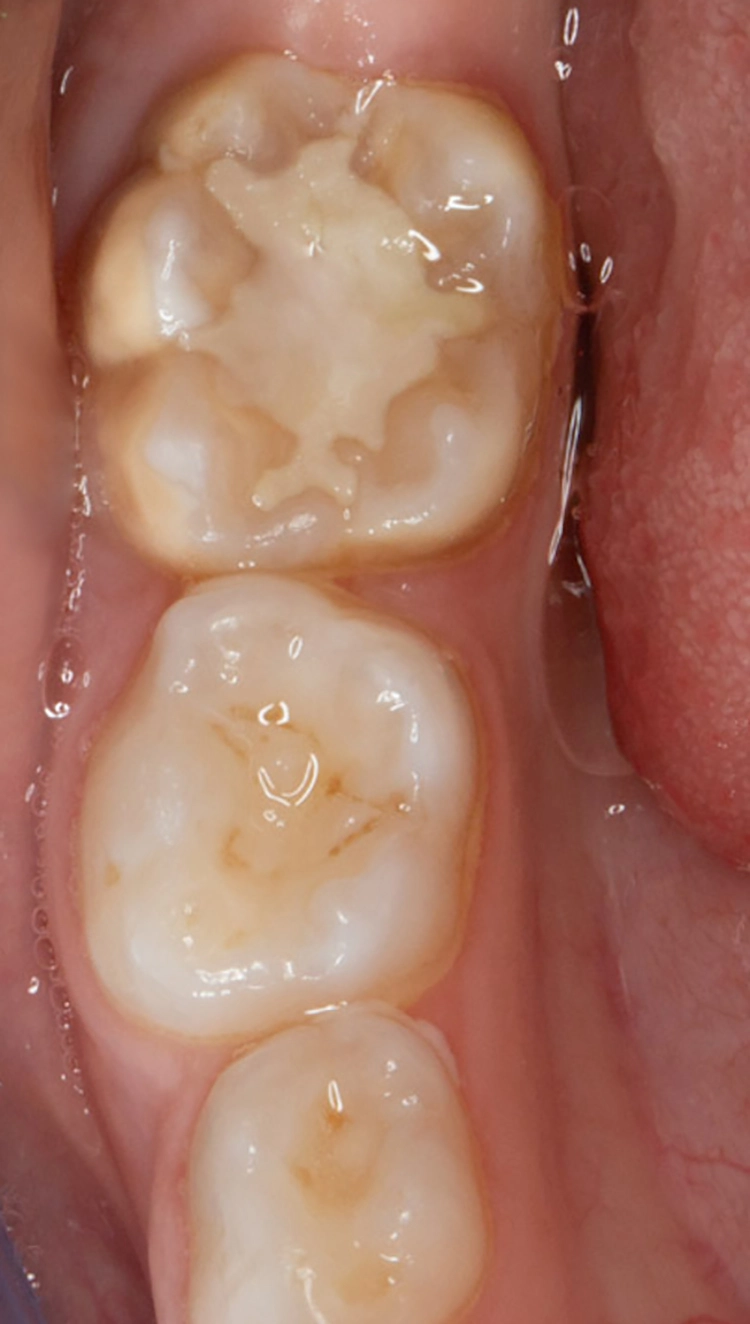

Bekes/BoukhobzaAbb. 2: Fissurenversiegelung an Zahn 36 mit umschriebenen Opazitäten.

Fissurenversiegelungen können bei MIH-Molaren generell dann durchgeführt werden, wenn diese keine posteruptiven Schmelzeinbrüche im okklusalen Bereich aufweisen und nicht kariös kavitiert sind [7] (Abb. 2). Es empfiehlt sich, vor der Applikation des Versiegelungsmaterials ein Adhäsiv anzuwenden, um den Verbund zum porösen, mindermineralisierten Schmelz zu verbessern [8–10]. Sollte der Zahn noch nicht vollständig eruptiert sein, kann auch ein niedrigvisköser Glasionomerzement zum Einsatz kommen.